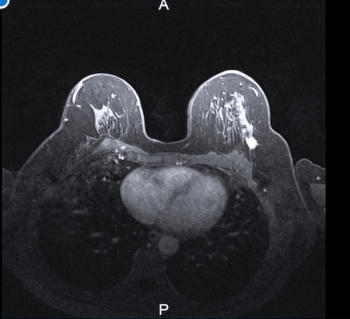

Additional carcinoma in the ipsilateral breast was detected on preoperative MRI exams in 24 out of 102 women prior to lumpectomy and mastectomy procedures, according to new study findings presented at the 2024 American Society of Clinical Oncology (ASCO) Annual Meeting in Chicago.